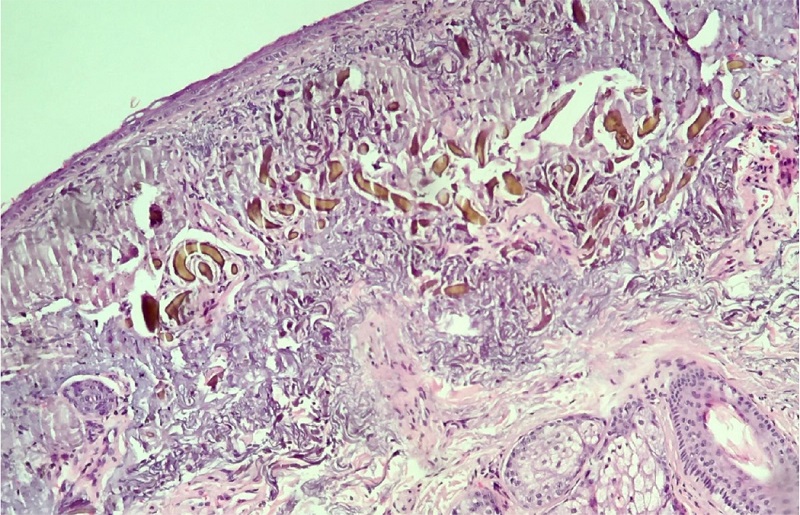

Mulher de 70 anos, fototipo IV, com queixa de “manchas na face há dez anos”. Ao exame dermatológico, apresentava na face (frontotemporal, malar e mandibular bilateral), cervical e colo, máculas hipercrômicas, bem delimitadas, de bordas irregulares, formadas pela confluência de pigmentação enegrecida-acinzentada com distribuição folicular, assintomáticas (Figura 1). Negava comorbidades e relatava uso prévio de formulação contendo tretinoína e hidroquinona para tratamento de melasma. Diante do quadro clínico, foram feitas as hipóteses diagnósticas de: líquen plano pigmentoso, ocronose exógena, dermatite de contato pigmentada e melanodermia tóxica. Foi realizada biópsia incisional em dois pontos e houve prescrição de dexametasona tópica associada à fotoproteção. O histopatológico mostrou epiderme retificada, derme com degeneração basofílica do colágeno, estruturas alongadas de coloração castanho-amarelada, derrame pigmentar e reação de corpo estranho focal em ambas as amostras (Figuras 2 e 3). Estes achados associados ao quadro cutâneo e à ausência de manifestações sistêmicas concluíram o diagnóstico de ocronose exógena. A paciente foi submetida à dermoabrasão com lixa d’água, por área facial acometida (Figura 4), associada ao uso de formulação tópica noturna contendo desonida 0,05%, tretinoína 0,01% e alfa bisabolol 2%, além de fotoproteção. Após três meses, houve clareamento expressivo (Figura 5). Paciente encontra-se em acompanhamento ambulatorial com resultado mantido.

A confirmação histopatológica é mandatória, exibindo derrame pigmentar, elastose solar, fibras amarelo-acastanhadas em formato de banana na derme papilar e eventual presença de degeneração do colágeno, mílio coloide e granulomas.1-4 A dermatoscopia pode corroborar o diagnóstico, mostrando estruturas irregulares, globulares, anulares ou arciformes, castanho-acinzentadas, distribuídas ao longo da lesão e que obliteram as aberturas foliculares.4,5,6